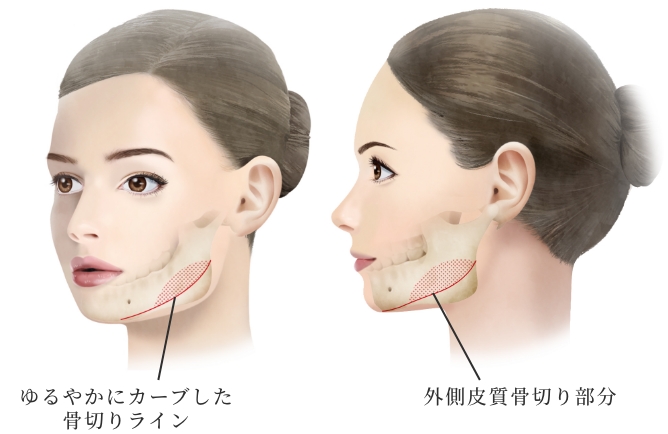

骨切りカッターを垂直に骨に当てるため、下顎角直前までスムーズなカーブラインの骨切りが可能。

スムーズなカーブを描く

骨切りが可能

骨切りカッターを骨面に垂直に当てることが出来るため、スムーズで自然なカーブを形成出来る。

骨切り部位は頬骨弓部から体部前面に至り、L字型に長く幅広く切除し頬骨全体を内下方へ移動するため、頬骨全体に縮小効果があります。L字型に合計4回の骨切りが必要なため、複雑で精密な手技が必要な施術です。